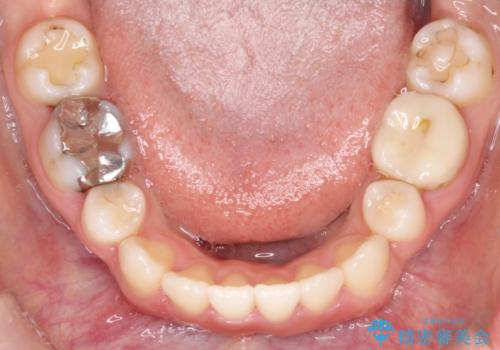

- 上下の歯の中心(正中)のズレと、口元の見た目を気にされて来院されました。精密な検査の結果、咬み合わせのバランスを整えながら、正中線を一致させる治療が必要と判断。患者様のご希望に合わせ、透明で目立ちにくいインビザライン(マウスピース矯正)による治療計画を立案しました。歯列全体を奥(遠心)へ移動させるためにゴムかけを併用。さらに、見た目を改善するため、既存の金属の被せ物をセラミッククラウンに交換することも治療計画に組み込みました。

今回の矯正治療では、透明なマウスピース型の装置インビザラインを使用しました。歯列を奥へ動かす遠心移動の効率を高めるため、患者様ご自身にゴムかけも行っていただきました。この併用によって、歯をより正確かつスムーズに動かすことができ、上下の歯の中心である正中線を一致させることが可能になりました。また、治療の最終段階では、以前から入っていた金属の被せ物を、天然歯に近い色合いのセラミッククラウンに交換。矯正治療と審美治療を組み合わせることで、機能的な咬み合わせの改善に加え、金属が見えない、より自然で美しい口元を獲得していただけました。